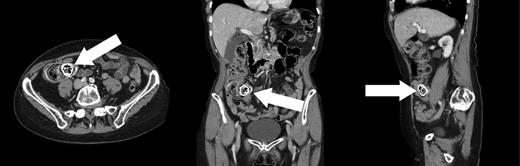

She subsequently had a colonoscopy, which revealed mild sigmoid diverticulosis and no mass lesions. The caecum appeared distorted by a large faecolith impacted in the appendiceal orifice. This was visible as an ovoid calcified lesion projected over the right sacral ala on a radiograph (Fig. 1) of the pelvis. A computed tomogram (Fig. 2) of the abdomen and pelvis demonstrated a giant calcified appendicolith, measuring 2.5 cm in its largest dimension, within the base of an otherwise normal appendix. Uncomplicated sigmoid diverticulosis was also noted.

Axial, coronal and sagittal CT views showing a giant appendicolith within the base of the appendix. Calcification and the laminar structure are well demonstrated on CT.